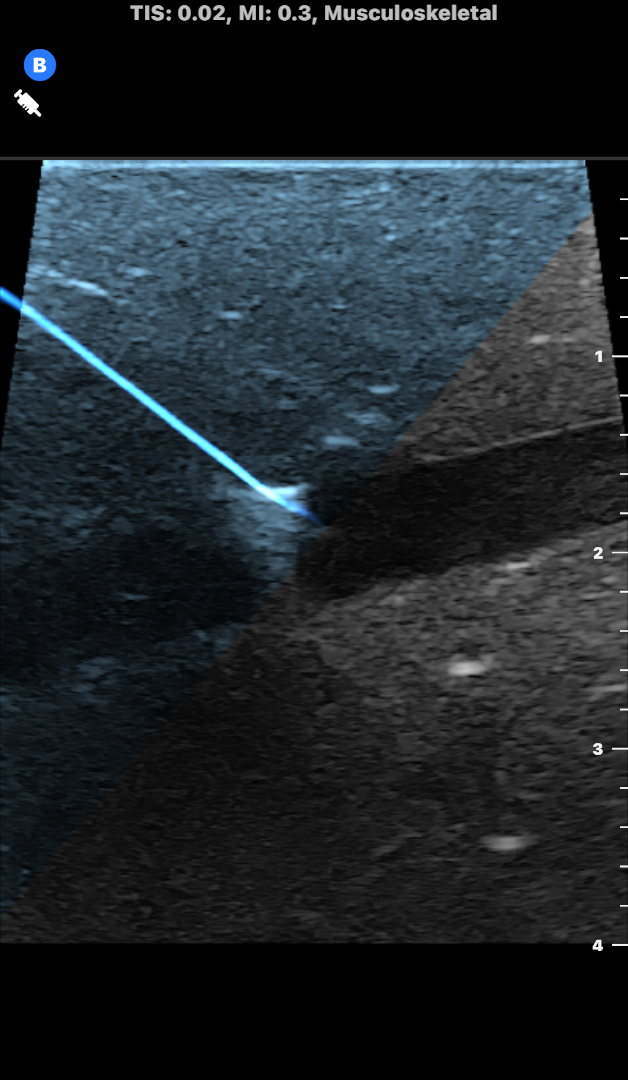

Interventional Ultrasound

• IV catheter placements

• IV access

• Peripheral nerve blocks

• Fine needle aspirates

• Joint injections

• Epidural injections

The innovative Needle Viz™ tool is now available to veterinarians within five clinical presets (Bladder, Musculoskeletal, Musculoskeletal Equine, Small Organ, and Vascular). The ability to visualize needles in-plane will help veterinarians perform more confident fine needle aspirates, and quickly place lines and injections with greater certainty in emergency care situations.